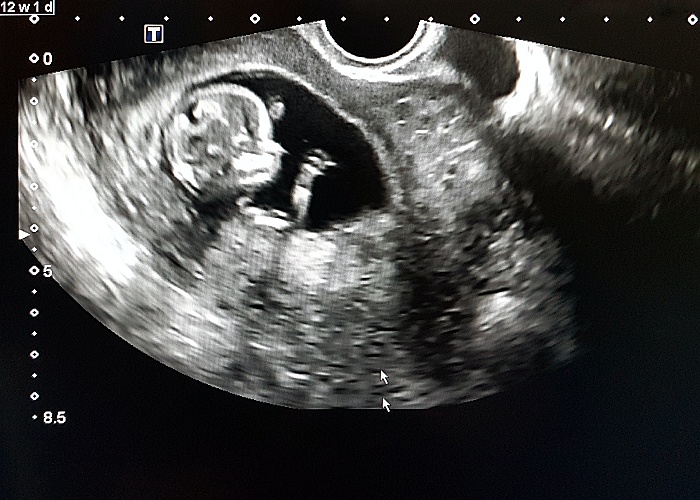

During an amnio, a needle is inserted through the abdominal wall into the uterus to extract a few teaspoons of the amniotic fluid surrounding the foetus. From this fluid, cells that the foetus has sloughed off during development are collected. During a CVS, a sample of the placenta is removed through the cervix or abdomen. With both amnio and CVS, testing is done to determine how many chromosomes are present in the foetus. These tests are highly accurate and diagnostic, but are also invasive and associated with some risks, including a small (<1%) risk of miscarriage.

Certified genetic counsellor Amanda Luedecke pointed out that collecting accurate outcome data on all patients who have an abnormal screen is challenging and laboratories often cannot collect that information. For that reason, the outcome data presented may be incomplete and inaccurate. Luedecke also said that patients who do receive an abnormal screen may then be candidates for insurance coverage of additional ultrasounds. For example, such ultrasounds are more likely to identify heart defects, if present, allowing the patient the opportunity to meet a paediatric cardiologist and to deliver in a centre with a paediatric surgeon, if necessary.